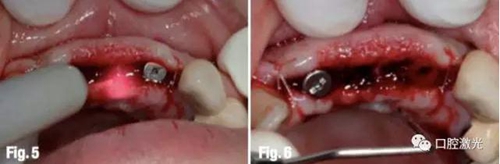

在打開的齦瓣兩端各縫一針,中間部分由于愈合基臺支撐而無需縫合(圖4)。利用口腔激光對齦瓣進行去上皮化處理。隨后需要在開放創(chuàng)口內(nèi)引導(dǎo)出血,該步驟可以通過鉺激光對骨膜削切后實現(xiàn)出血或者利用手術(shù)刀進行軟組織切割。待血液充滿創(chuàng)口后,利用半導(dǎo)體激光進行凝血照射。激光功率8W,脈沖模式,50%占空比,采用生物刺激頭或者使光纖尖遠離創(chuàng)口(采用光纖時須適當降低功率),形成大約5mm直徑的光斑進行照射(圖5)??捎^察到待血液呈深粉紅色半凝固時(溫度為60-80℃)操作完成(圖6)。

注意在利用激光照射凝血時,不要固定某個位置不動,否則血液溫度過高后會形成黑色的碳化層(溫度大于100℃)。